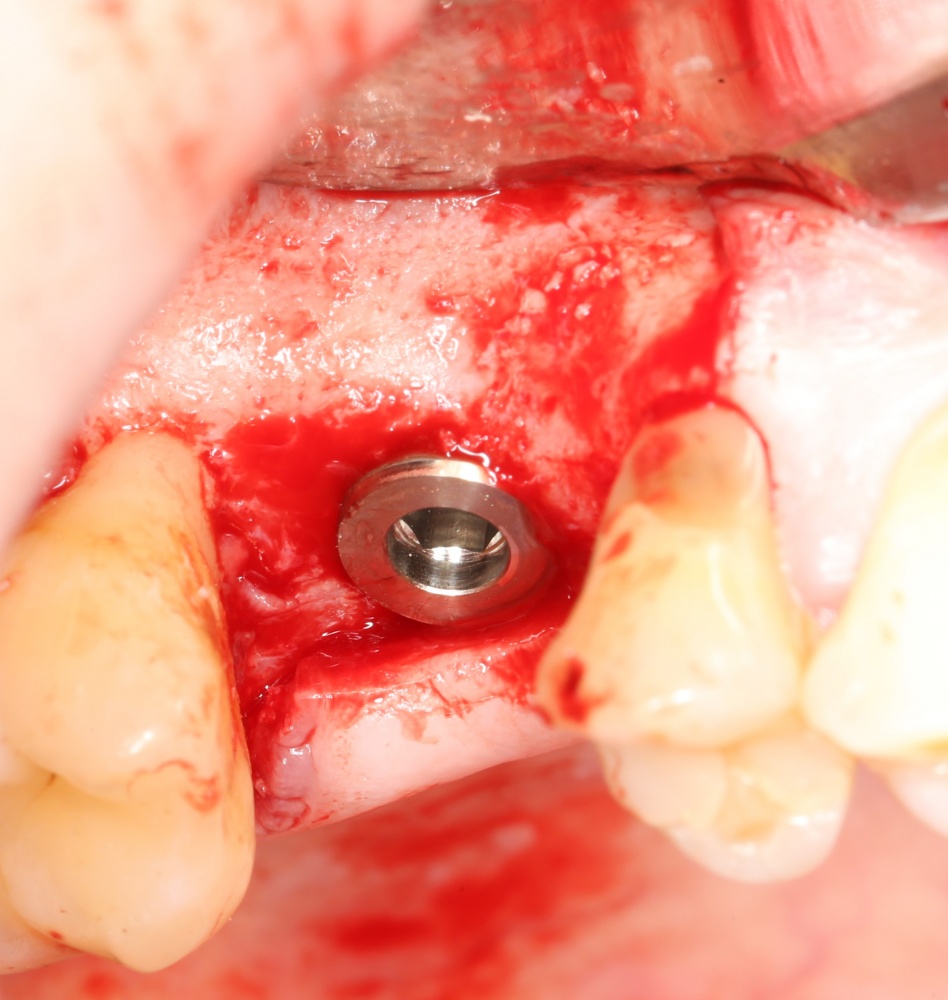

Кстати, обрати внимание на ширину альвеолярного гребня (левая картинка). Она чуть меньше 3 мм. Это объясняет, почему я засомневался в возможности установки имплантатов одновременно с остеопластикой. Понятно и без КЛКТ.

Возвращаемся к основной операционной области. Еще раз посмотрим на альвеолярный гребень, поофигеваем от его ширины и моих грандиозных планов:

Я зафиксировал костный блок практически без адаптации на несколько винтов. Обрати внимание, что винты находятся в зоне, где не планируется установка имплантатов. Фиксация должна быть надежной, поскольку мне еще предстояла подготовка лунок для имплантатов. Трех винтов для этого вполне достаточно.

Напомню, что для этой работы я выбрал субкрестальные имплантаты Ankylos C/X. Они прекрасно сочетаются с любым методом остеопластики.

Глянем на то, что получилось: